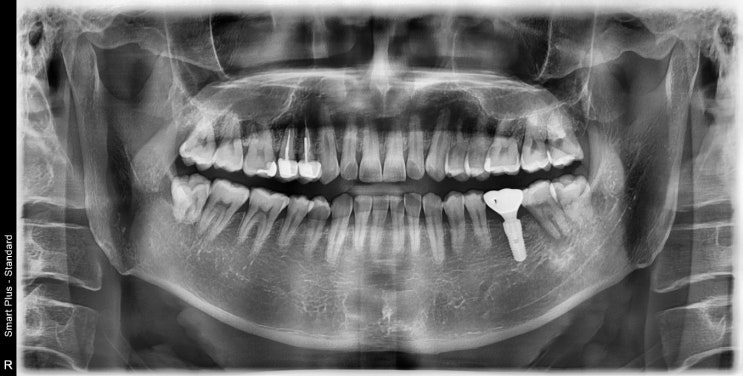

오산충치치료 단계별로 치료방법이 달라지기 때문에 정확한 검진이 필요 합니다.

안녕하세요. 오산 서울홍진선치과 입니다. 치아는 아무리 단단하다고 하더라도 여러가지 이유로 상실될 수 ...

동탄목동치과, 임플란트를 하기전 반드시 확인해야할 "이것"

안녕하세요. 오산 서울홍진선치과 입니다. 치아는 한번 손상이 되면 자연적으로 회복이 되지 않기 때문에 ...

평택임플란트잘하는곳, "이것"만 확인하면 실패할 확률이 낮아 집니다.

안녕하세요. 오산 서울홍진선치과 대표원장 홍진선입니다. 치아는 한번 손상이 되거나 소실이 되면 스스로 ...